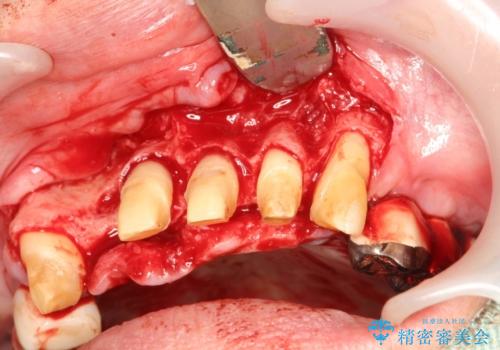

- 歯周病により欠損が生じた歯槽骨、まずは再生治療をおこなう

→治癒後、確定外科を行い完全に歯周ポケットを除去し、最終的に歯周補綴をおこなう

歯周病が進行してしまうと、歯周外科による処置が不可欠になります。

様々なリスクがありますが、唯一歯周病を除去することが可能な手段です。